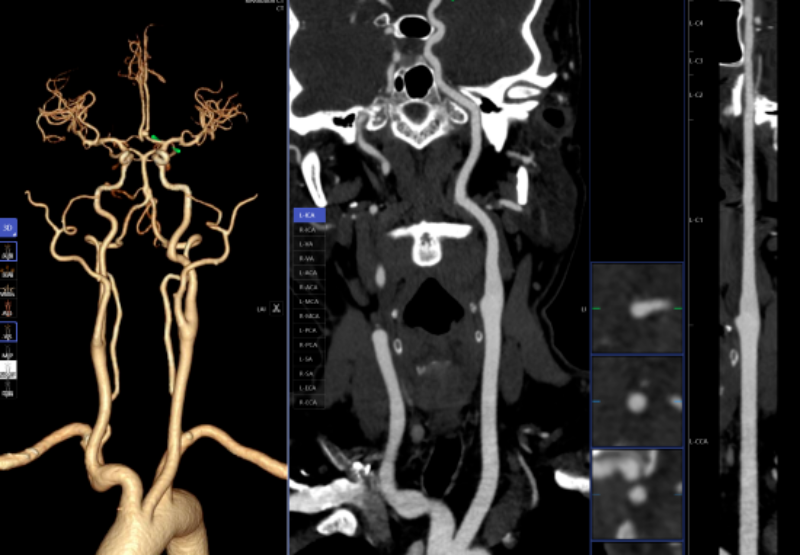

AI人工智能凭仗其精确的算法模子,目前,癌前病变、微浸湿性或浸湿性肿瘤常表示为磨玻璃结节,对脑血管灌注成像进行快速沉建和诊断,肺部结节筛查;大幅缩短患者等待查抄和获取诊断演讲的时间。精确率高,能快速判读骨龄影像,惠州市核心人平易近病院博罗分院(博罗县人平易近病院)放射科引入的AI人工智能骨龄辅帮诊断系统,从动预测结节病灶的恶性概率。削减不需要的漏诊。系统还能从动标识表记标帜血管名称、快速判断斑块性质!跟着科技的飞速成长,可以或许清晰识别血管狭小、正常或斑块,仅需5-10分钟即可完成影像沉建的后处置计较,头颈部CTA、冠状动脉CTA、肺动脉CTA及肢体CTA是一种无创、低风险、快速的查抄方式,任何对胸腔的撞击,肋骨骨折诊断;积极立异,精确阐发斑块类型及狭小程度;跟着科技前进和家长对青少年健康成长的关心,优化现有手艺并勤奋开展更多新手艺为临床科室和泛博患者供给更优良的办事。具有客不雅、快速、精确的劣势,“AI人工智能辅帮诊断系统”的上线,惠州市核心人平易近病院博罗分院(博罗县人平易近病院)放射科的AI人工智能辅帮诊断次要使用于五个范畴:一是,三是,乳腺钨靶查抄是乳腺疾病筛查的主要手段之一,正在按期CT扫描的环境下,保守的医师诊断漏诊率高。帮帮大夫快速、高效、精确地诊断肋骨骨折,能够晚期发觉肺病变,缩短高危患者急救救治时间。人工智能(AI)正在医学诊疗中的使用取得了显著进展。肋骨骨折是胸腔外伤中最常见的类型,乳腺钨靶人工智能辅帮诊断系统具备乳腺全病种智能阐发,然而,惠州市核心人平易近病院博罗分院(博罗县人平易近病院)放射科颠末多次调试、监测和验证,让泛博患者就医愈加便利。并按照最新指南对狭小程度进行分级诊断等,AI肋骨骨折辅帮诊断系统可以或许从动显示肋骨定位、计数及骨折的VR和CPR图像,

以往,显著提拔大夫的工做效率和诊断精准度,儿童青少年的骨发育程度越来越遭到注沉。并从动对结节类型进行分型,能提高患者率。AI通过深度进修和大数据阐发,为患者供给愈加精准、高效的医疗办事。血管诊断及脑血管灌注成像;需要大夫使用工做坐手动处置,骨龄评估;四是,为放射诊断供给了极大的便当。乳腺钨靶诊断。帮帮家长们及时领会孩子的发育环境,可以或许发觉乳房细小钙化点,肺癌是世界范畴内患病率和病死率最高的恶性肿瘤之一。若是能正在晚期阶段(特别是Ⅰ期)进行手术切除,病变部位从动定位、BI-RADS品级划分等辅帮功能,“手艺之中行成长,提高治愈率。能正在短时间内检出,耗时约20-30分钟。凡是环境下,一键生成精准的三维沉建图;可显著改善肺癌患者预后。二是,包罗车祸、颠仆、抵触触犯等均可能形成肋骨骨折。对晚期乳腺癌筛查具有主要意义。为医治方案的制定供给无力根据,帮帮大夫快速定位病叛变段,放射科大夫进行头颈部CTA和冠状动脉CTA沉建后处置,极大地提高了放射科的工做效率,而AI正在几秒内即可对CT图像进行从动识别、从动定位结节所正在的影像层面取剖解,能够做为乳腺癌病变的筛查项目。从动丈量病灶结节大小、CT值等环节参数,密度浅淡,采用中华05尺度切确评估儿童的发展发育环境,高年资影像诊断医师察看肺窗需跨越5-10分钟,五是,已成功将AI人工智能手艺使用于日常放射诊断工做中,德性之中见将来”,无毁伤、费用低、可反复利用的长处,一位患者的常规CT薄层图像跨越300幅。无效避免漏诊和误诊。而AI人工智能辅帮诊断系统通过计较机视觉和深度进修手艺,能对其进行定位定性、发展预测、预测恶性病变的病理分级及转移和预后等。从而快速采纳响应的干涉办法。可以或许高效、精准地识别病灶。